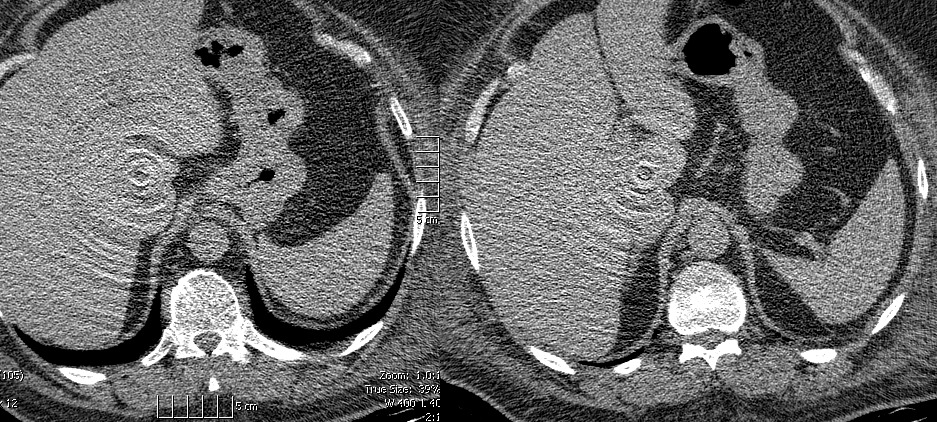

左右髋关节假体左右髋关节假体会导致伪影降低骨盆图像质量

植入牙植入牙科填充物会导致伪影降低牙齿图像质量